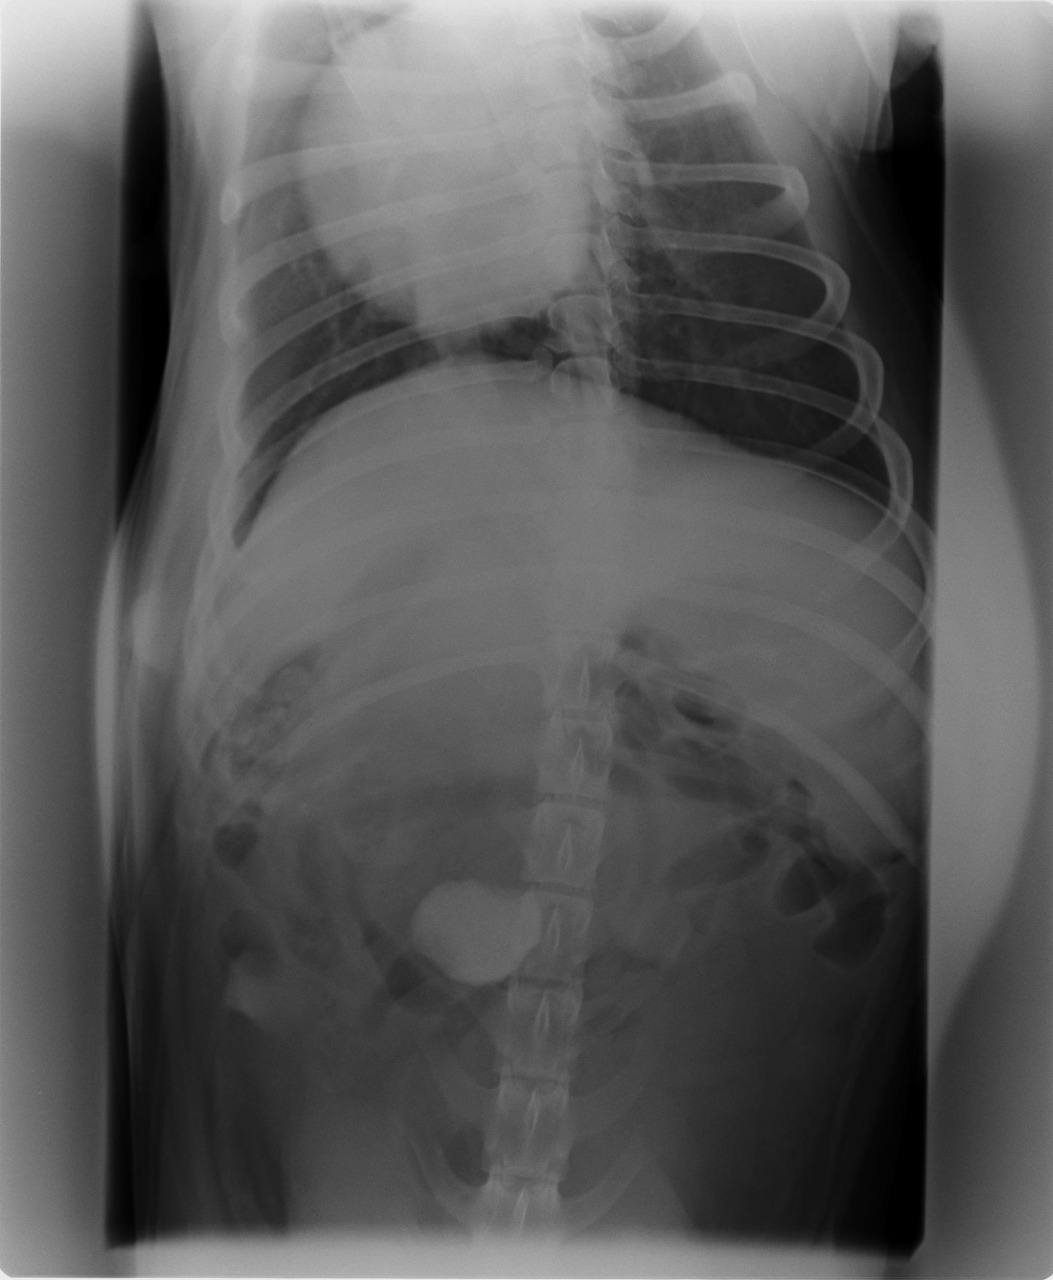

A Shain é uma linda labradora de 4 anos que pariu no dia 09/08. Três dias depois a Shain veio à consulta pois apresentava uma apatia extrema e não queria comer nada, nem sequer os bolos que tanto gosta!! Apresentava uma temperatura muito elevada e dor. Ao exame clínico não se notava mais nenhuma alteração para além destes sintomas. O dono, entretanto, refere que a Shain tem o hábito de brincar com pedras e que, por vezes, engole-as. Fizemos o rx abdominal e lá estava a causa da apatia da Shain: uma pedra na zona da válvula ileo-cecal!